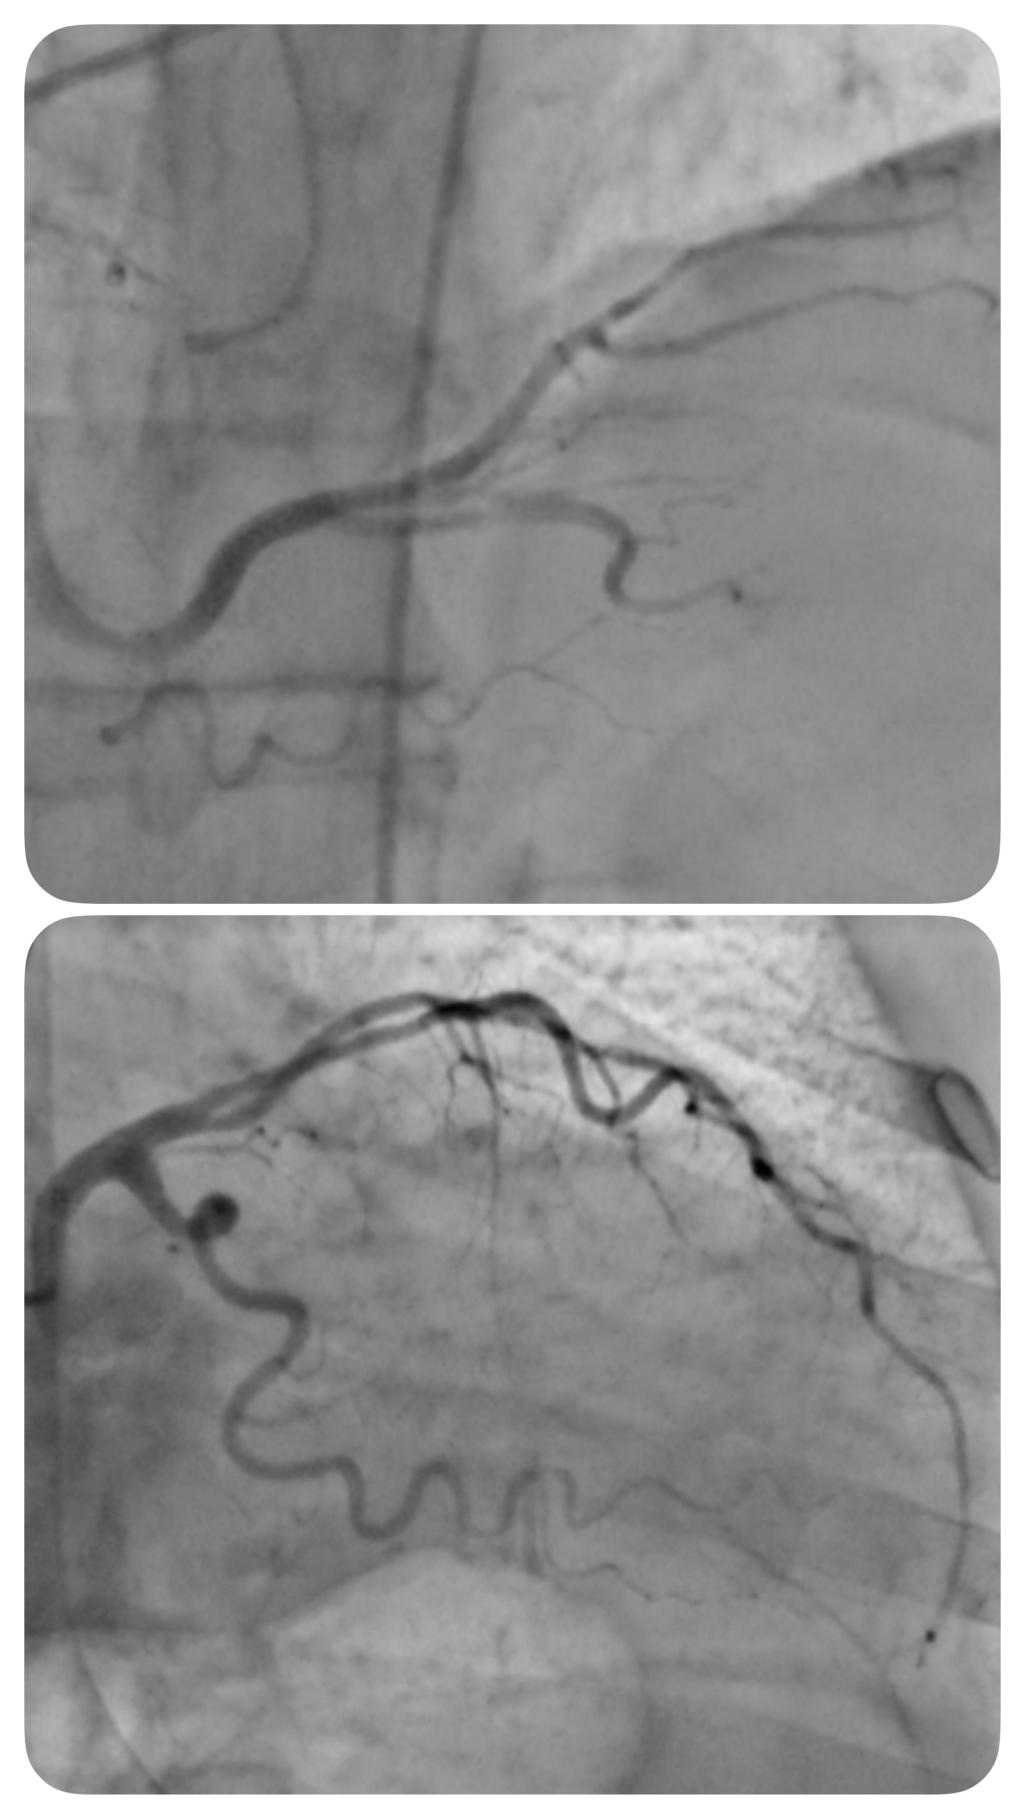

此次首例脑血管造影的顺利开展,正是科室同质化建设的重要成果。术前,程率芳主任带领团队完善术前讨论、制定周密方案;术中,姬令山副主任现场指导,团队配合默契,精准完成操作,整个过程顺利流畅,为患者后续诊疗提供了清晰可靠的诊断依据。同时,科室还响应“泛血管病”诊疗理念,联合心病科完成了脑血管-冠脉联合造影,实现了心脑血管疾病的同步评估,为合并心脑血管共病的患者提供了一站式诊疗服务。